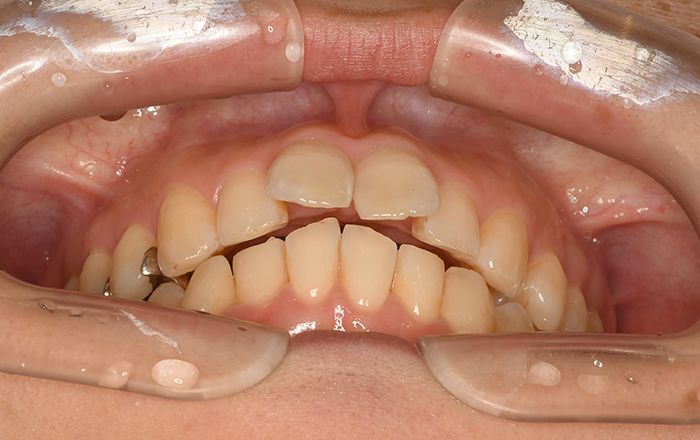

舌の癖があると歯並びに悪影響を与えます。

普段過ごしている時に、舌が正しいポジションでないと、歯並びが崩れたり、口呼吸の原因になってしまいます。

舌が影響した歯並びを3つご紹介します。

1)開咬

2)下顎前突(受け口)

3)上顎前突(出っ歯)